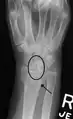

Scapholunate ligament disruption associated with a Colles' fracture